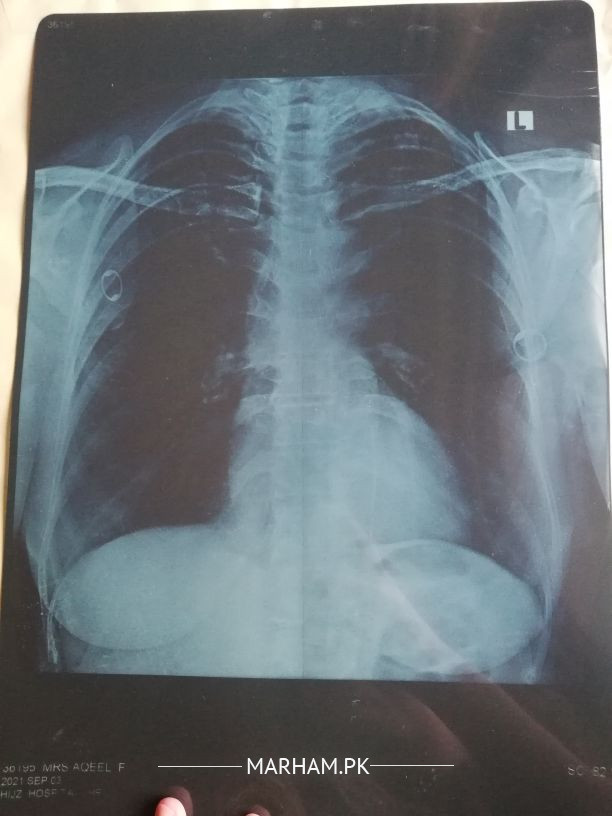

My mother is having dry cough no other symptoms no fever. Got her covid test today. Report is pending. Please check this x ray.

send me other investigation. no clear find of covid

what is oxygen saturation?X Ray seems to be normal.But X Ray is not diagnostic test For COVID.High Resolution CT (HRCT) Chest is Diagnostic For COVID .other tests which are helpful in diagnosis and disease severity are CBC, CRP,D Dimer